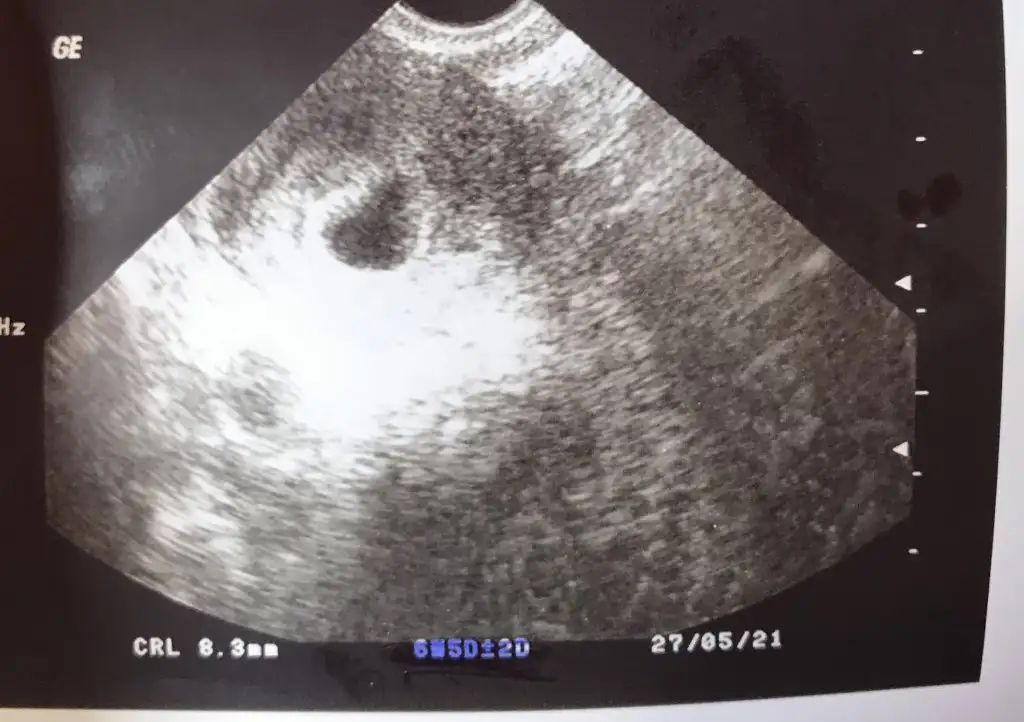

Hemen telaş etme ben ilk gebeliğimde 7+0 da zor görünmüştü bebek kalbi de zor duymuştuk, geç döllenmeden dolayı geriden gelmişti, belki öyle bi durum vardır, dua edelim bi sonraki görüşmede her şeyin yolunda olduğunu duyman içinKızlar bebeğini görebilen var mı? Ben dün doktora gittim kese baya büyümüş ama bebeğe dair hiçbir şey yok haftaya da göremezsek kürtaj dediler çok korkuyorum ya

Siz kaç haftaliksiniz da haftaya olmazsa kürtaj denildi adet tarihiniz nedir acabaKızlar bebeğini görebilen var mı? Ben dün doktora gittim kese baya büyümüş ama bebeğe dair hiçbir şey yok haftaya da göremezsek kürtaj dediler çok korkuyorum ya

Selam canım bende sadece keseyi gördüm o da çok küçüktü. Ama kalp atışı 7.haftada ancak duyulur canım korkma. O da niye hemen kürtaj demişKızlar bebeğini görebilen var mı? Ben dün doktora gittim kese baya büyümüş ama bebeğe dair hiçbir şey yok haftaya da göremezsek kürtaj dediler çok korkuyorum ya

26 ağustos son adet tarihim ben de çok şaşırdım hemen kürtaj denmesine asla istemiyorum olmayıSiz kaç haftaliksiniz da haftaya olmazsa kürtaj denildi adet tarihiniz nedir acaba

Ben de keseyi gördüm vajinal ultrasonla ama baya büyük kese ondan çok endişelendimSelam canım bende sadece keseyi gördüm o da çok küçüktü. Ama kalp atışı 7.haftada ancak duyulur canım korkma. O da niye hemen kürtaj demiş

Siz başka bi doktora daha görünün bence. Hemen 7.haftada kürtaj ol denmez benim bildiğim en azından 8.hafta da beklenir. Çünkü 7 de ancak duyuluyor kalp atışı.Ben de keseyi gördüm vajinal ultrasonla ama baya büyük kese ondan çok endişelendim